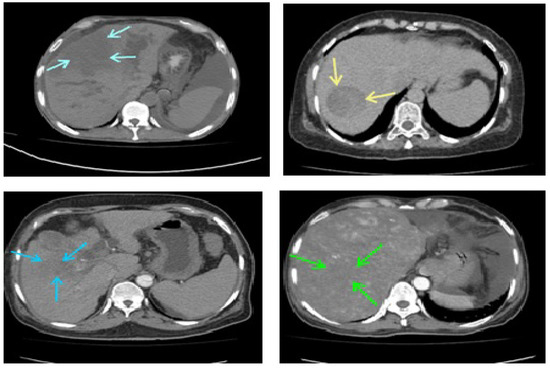

The inclusion criteria were the collection of data from infected patients with hepatitis B and C, a metastatic tumor (secondary tumor), tumor necrosis, or vascular disorder because of the availability of said data types. Patients on ventilators and renal function tests or who were children were excluded from the current study. Due to the low socioeconomic status of the area, biopsy to the confirm clinical data was impossible for the patients. The gold standard for the final diagnosis was serum alpha-fetoprotein and triphasic multidetector computed tomography of the liver, in which non-ionic intravenous ultravist contrast was used to enhance the diseased pattern. Table 1 shows the demographic data of the patients selected for the study. Figure 1 and Figure 2 show some images of our collected database. Figure 1 shows images with some abnormalities at some stages. Figure 2 compares normal case images with infected data.

Figure 2.

Construction of ROIs for the conventional machine learning methodology. Column 1: CT image of a normal class 1 liver versus an infected liver; column 2: CT image of a normal class 2 liver versus a metastatic liver, column 3: CT image of a normal class 3 liver versus a metastatic liver; column 4: CT image of a normal class 4 liver versus an abnormal vascular area in the liver.